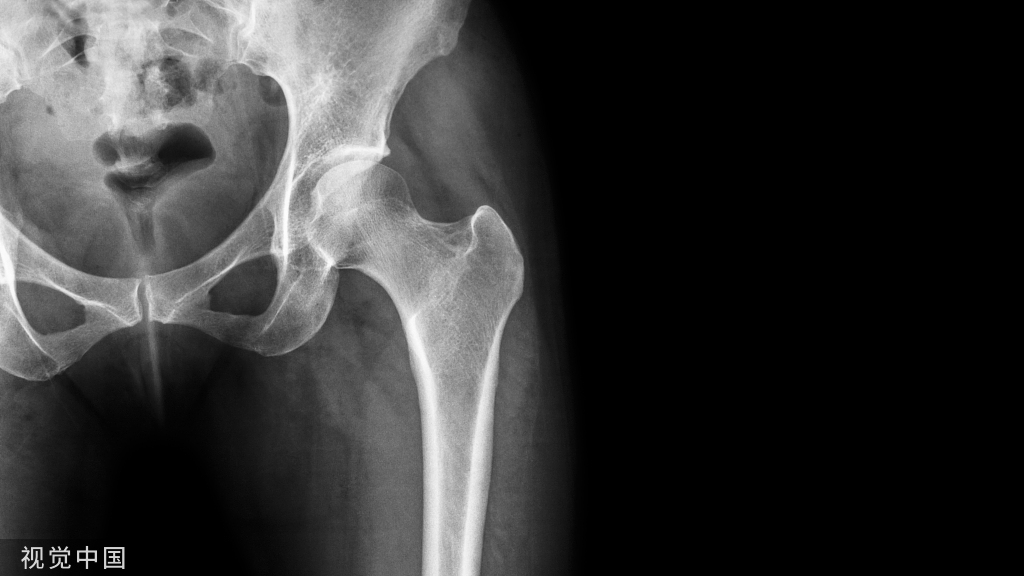

对于复杂髋内翻严重的骨折,可以适当内移进钉点到卵圆窝从而避免髋内翻。

同时注意钉子直钉弯钉的进针点不一致的问题。